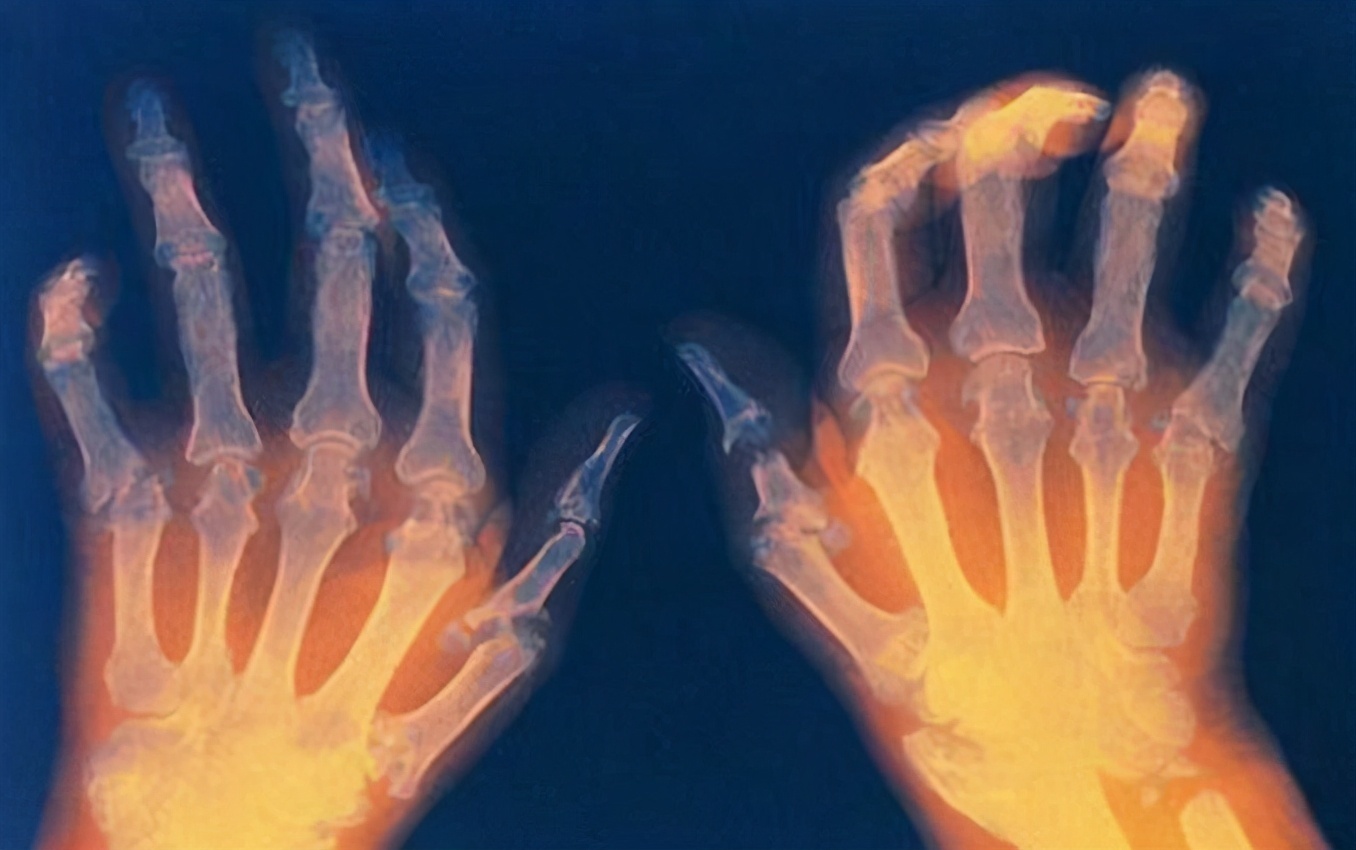

风湿性疾病

风湿性疾病是一类疾病,其临床表现复杂多样,不同疾病症状特点各异,由于目前医学对风湿病的认识较浅,发病机制尚不明确,因此目前不能根治。

还是那句话不能根治不等同于无法治疗,通过科学、系统、规范的治疗绝大多数风湿病可以处于稳定状态,患者能够像正常人一样生活以及工作。

但由于风湿病治疗周期长,药物起效慢,很多患者短期内看不到效果,部分患者转而寻求所谓的“特效药”、“祖传秘方”等,最终既导致大量的金钱损失又耽误了疾病治疗。